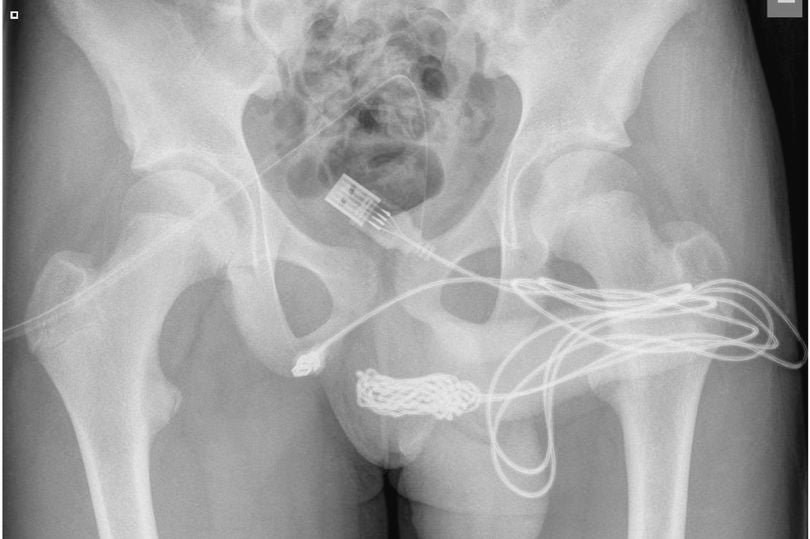

Ein Jugendlicher hat sich ein USB-Kabel in seinem Penis eingeklemmt, so dass die Ärzte es chirurgisch entfernen mussten. Der 15-jährige Junge versuchte Berichten zufolge, in einer bizarren Form von "sexuellen Experimenten" mit dem Kabel das Innere seiner Genitalien zu vermessen, bevor es sich verknotete und nicht mehr zu entfernen war. Nachdem sich das Kabel verknotet und verheddert hatte, begann der Junge, Blut in seinem Urin zu sehen. Schließlich brachte ihn seine Mutter ins Krankenhaus, wo er gestand, dass er das Kabel absichtlich eingeführt hatte.

Die Ärzte schrieben in dem Science Direct-Bericht: "Es wurde festgestellt, dass die beiden distalen Anschlüsse des USB-Kabels aus dem äußeren Harnröhrengang herausragen, während der mittlere Teil des verknoteten Kabels in der Harnröhre verblieb. Der Patient war ein ansonsten fitter und gesunder Jugendlicher ohne psychische Probleme in der Vorgeschichte."

Die Ärzte konnten das Kabel nicht mit einem Metallstab entfernen, da sich zu viele Knoten gebildet hatten, so dass sich der Junge einer Operation unterziehen musste. Die Ärzte machten einen Schnitt zwischen den Genitalien und dem Anus des Jungen, um an das Kabel zu gelangen, und legten einen Katheter an. Die Ärzte erklärten: "Über dem tastbaren Fremdkörper wurde ein Längsschnitt in den Peno-Skrotalbereich gemacht und das Gewebe vorsichtig durchtrennt, wobei der Bulbospongiosus-Muskel gespalten wurde. Beide Enden des Drahtes wurden erfolgreich durch den äußeren Harnröhrengang herausgezogen."